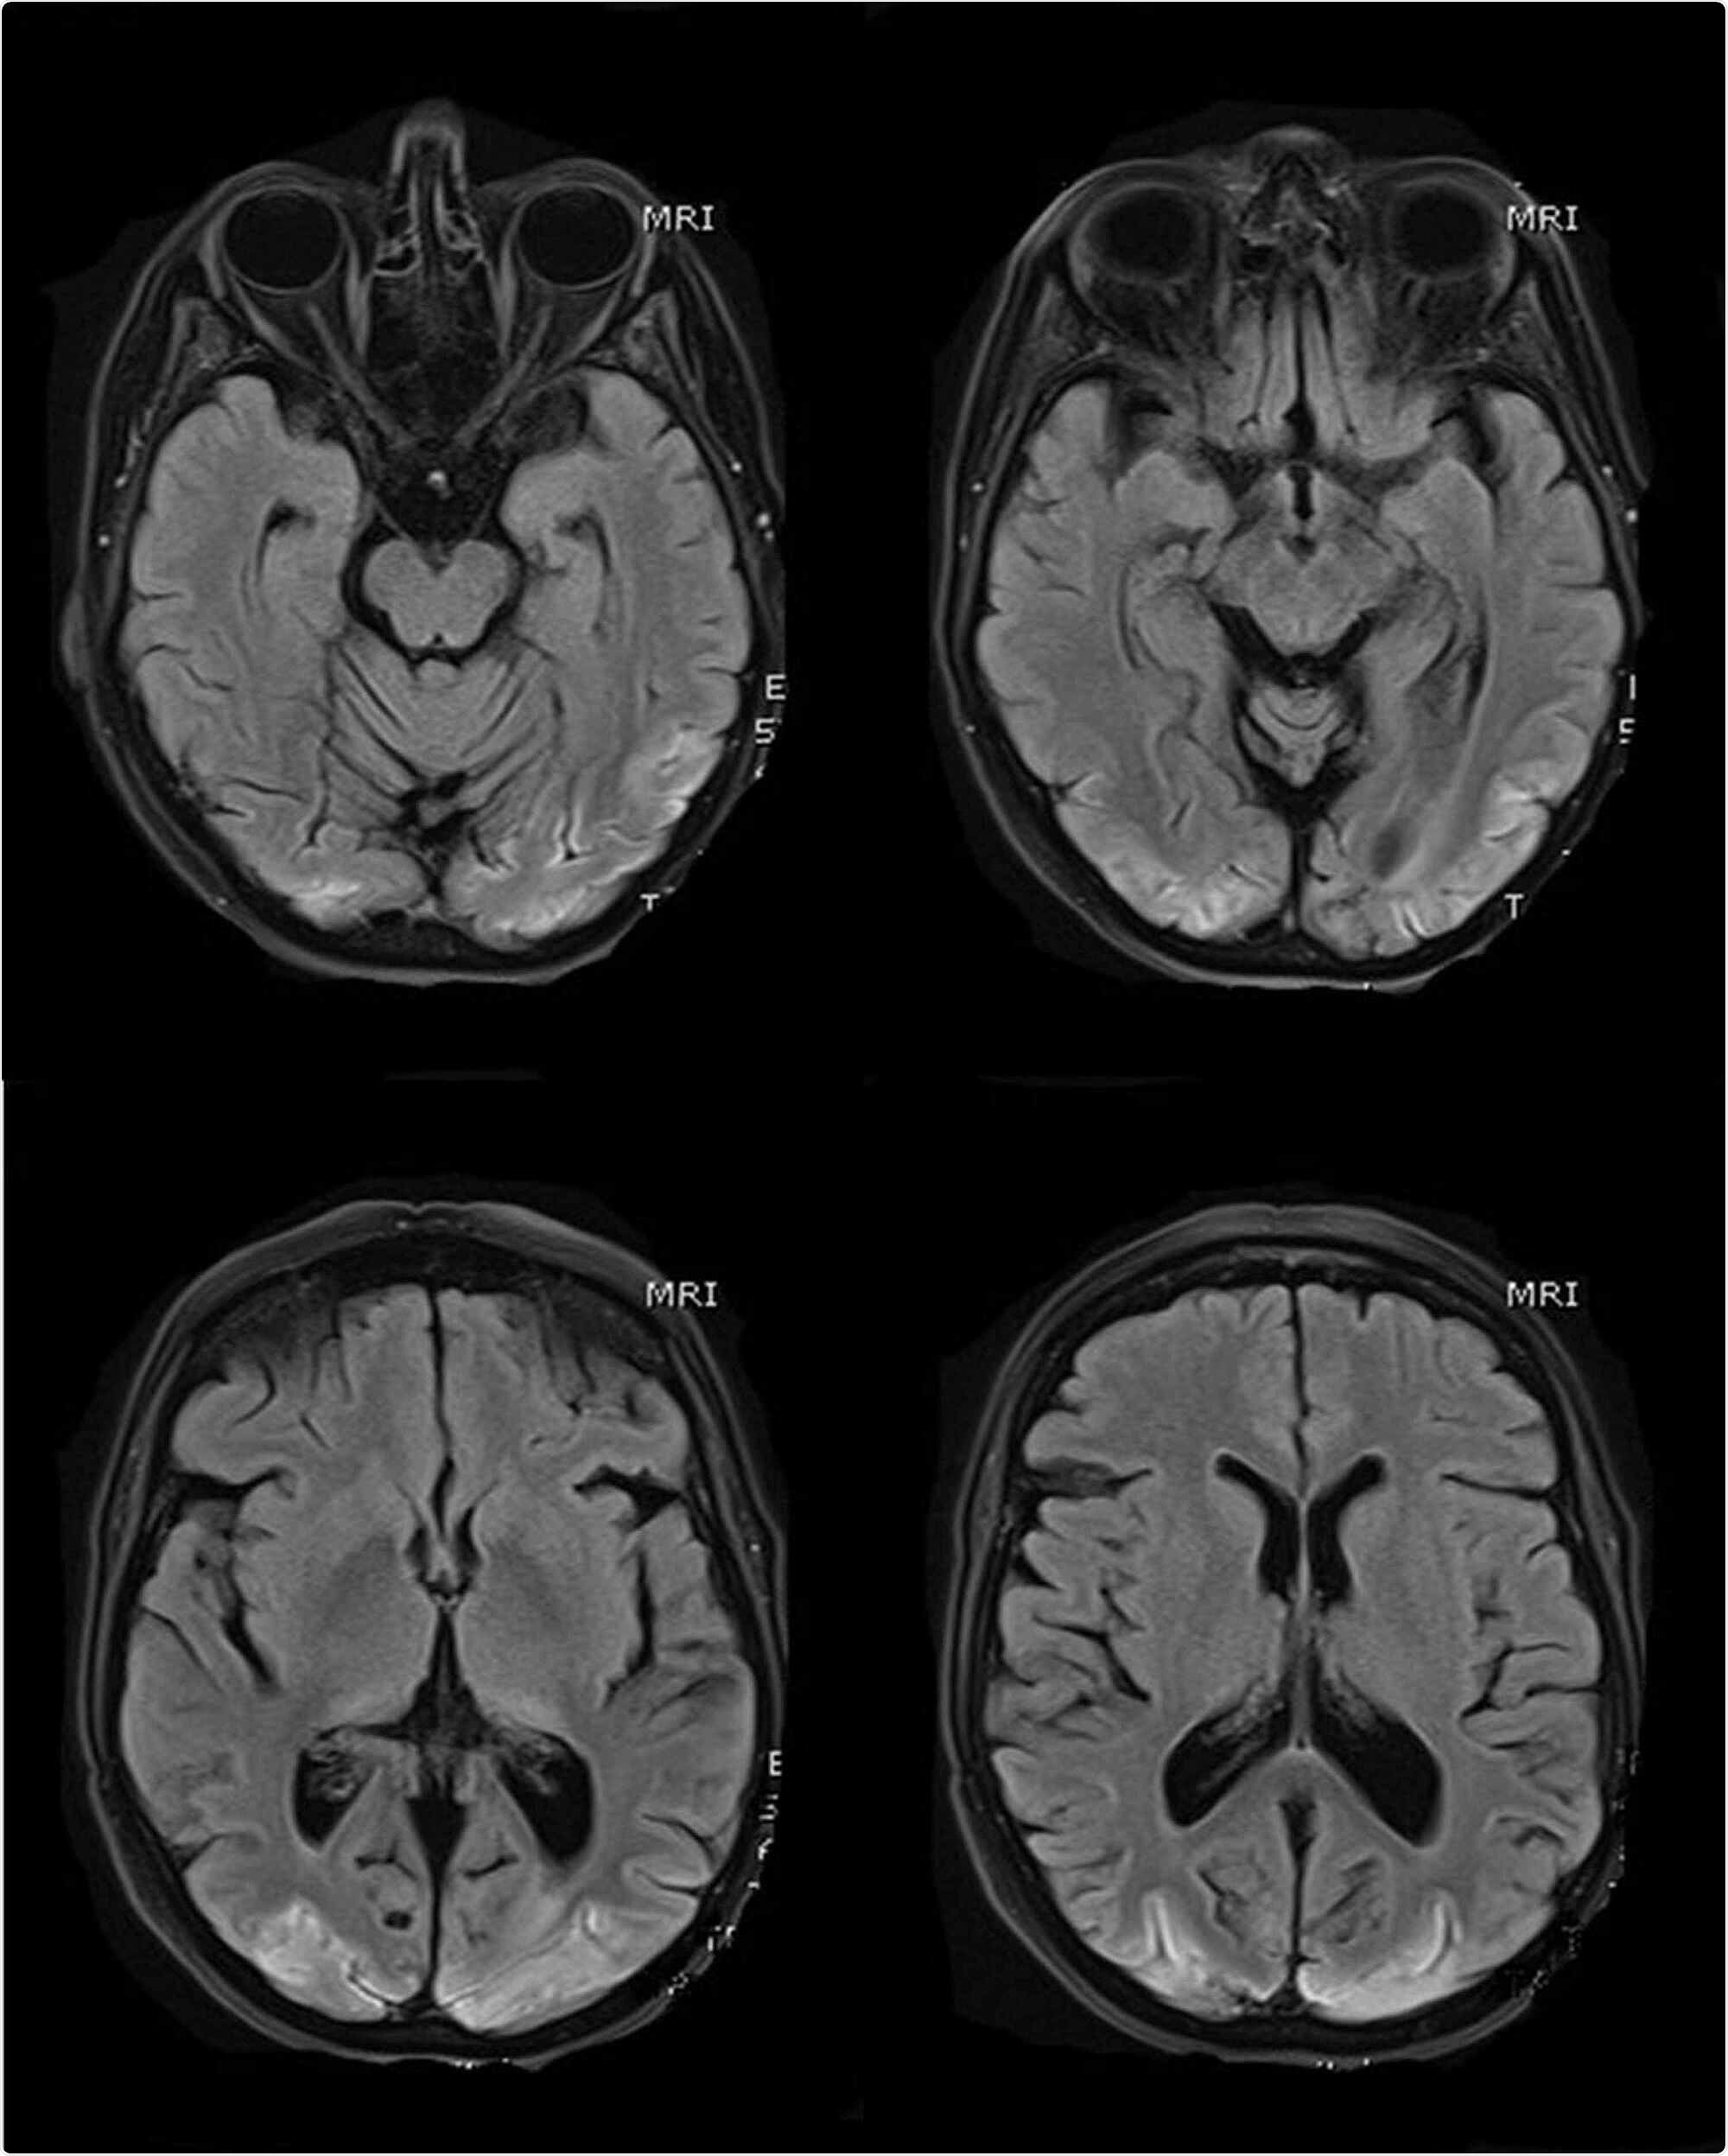

MR scans of the brain (selected T1 sequences) show bilateral symmetrical hyper-intensity involving the bilateral occipital lobe cortex; the changes are consistent with cortical pseudo-laminar necrosis as a complication of posterior reversible encephalopathy syndrome (PRES)

On day 21, the patient had a generalized seizure and a brain CT scan was performed, which suggested the possibility of PRES. Although the patient gradually became stabilized and the mechanical ventilation was removed, neurological examination demonstrated the presence of complete cortical blindness and Anton's syndrome (denial of loss of vision). Although the patient started recognizing shapes and colors because of gradual physical and neurological recovery, a significant level of visual impairment persisted.